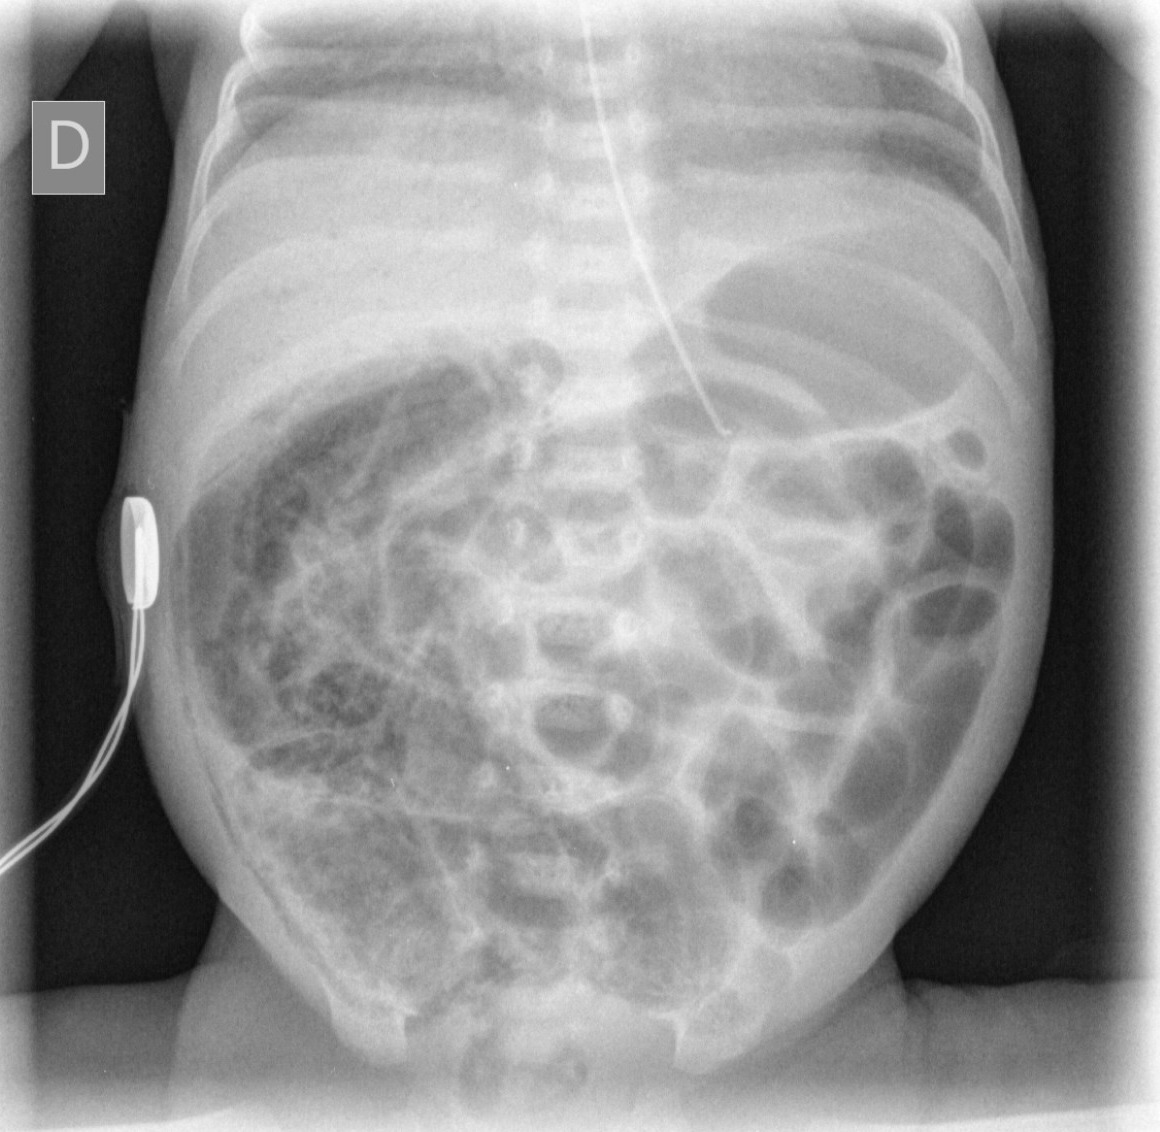

Peut compliquer la ventilation à haute pression nécessaire pour maintenir un volume courant élevé. À éliminer par une radiographie de thorax